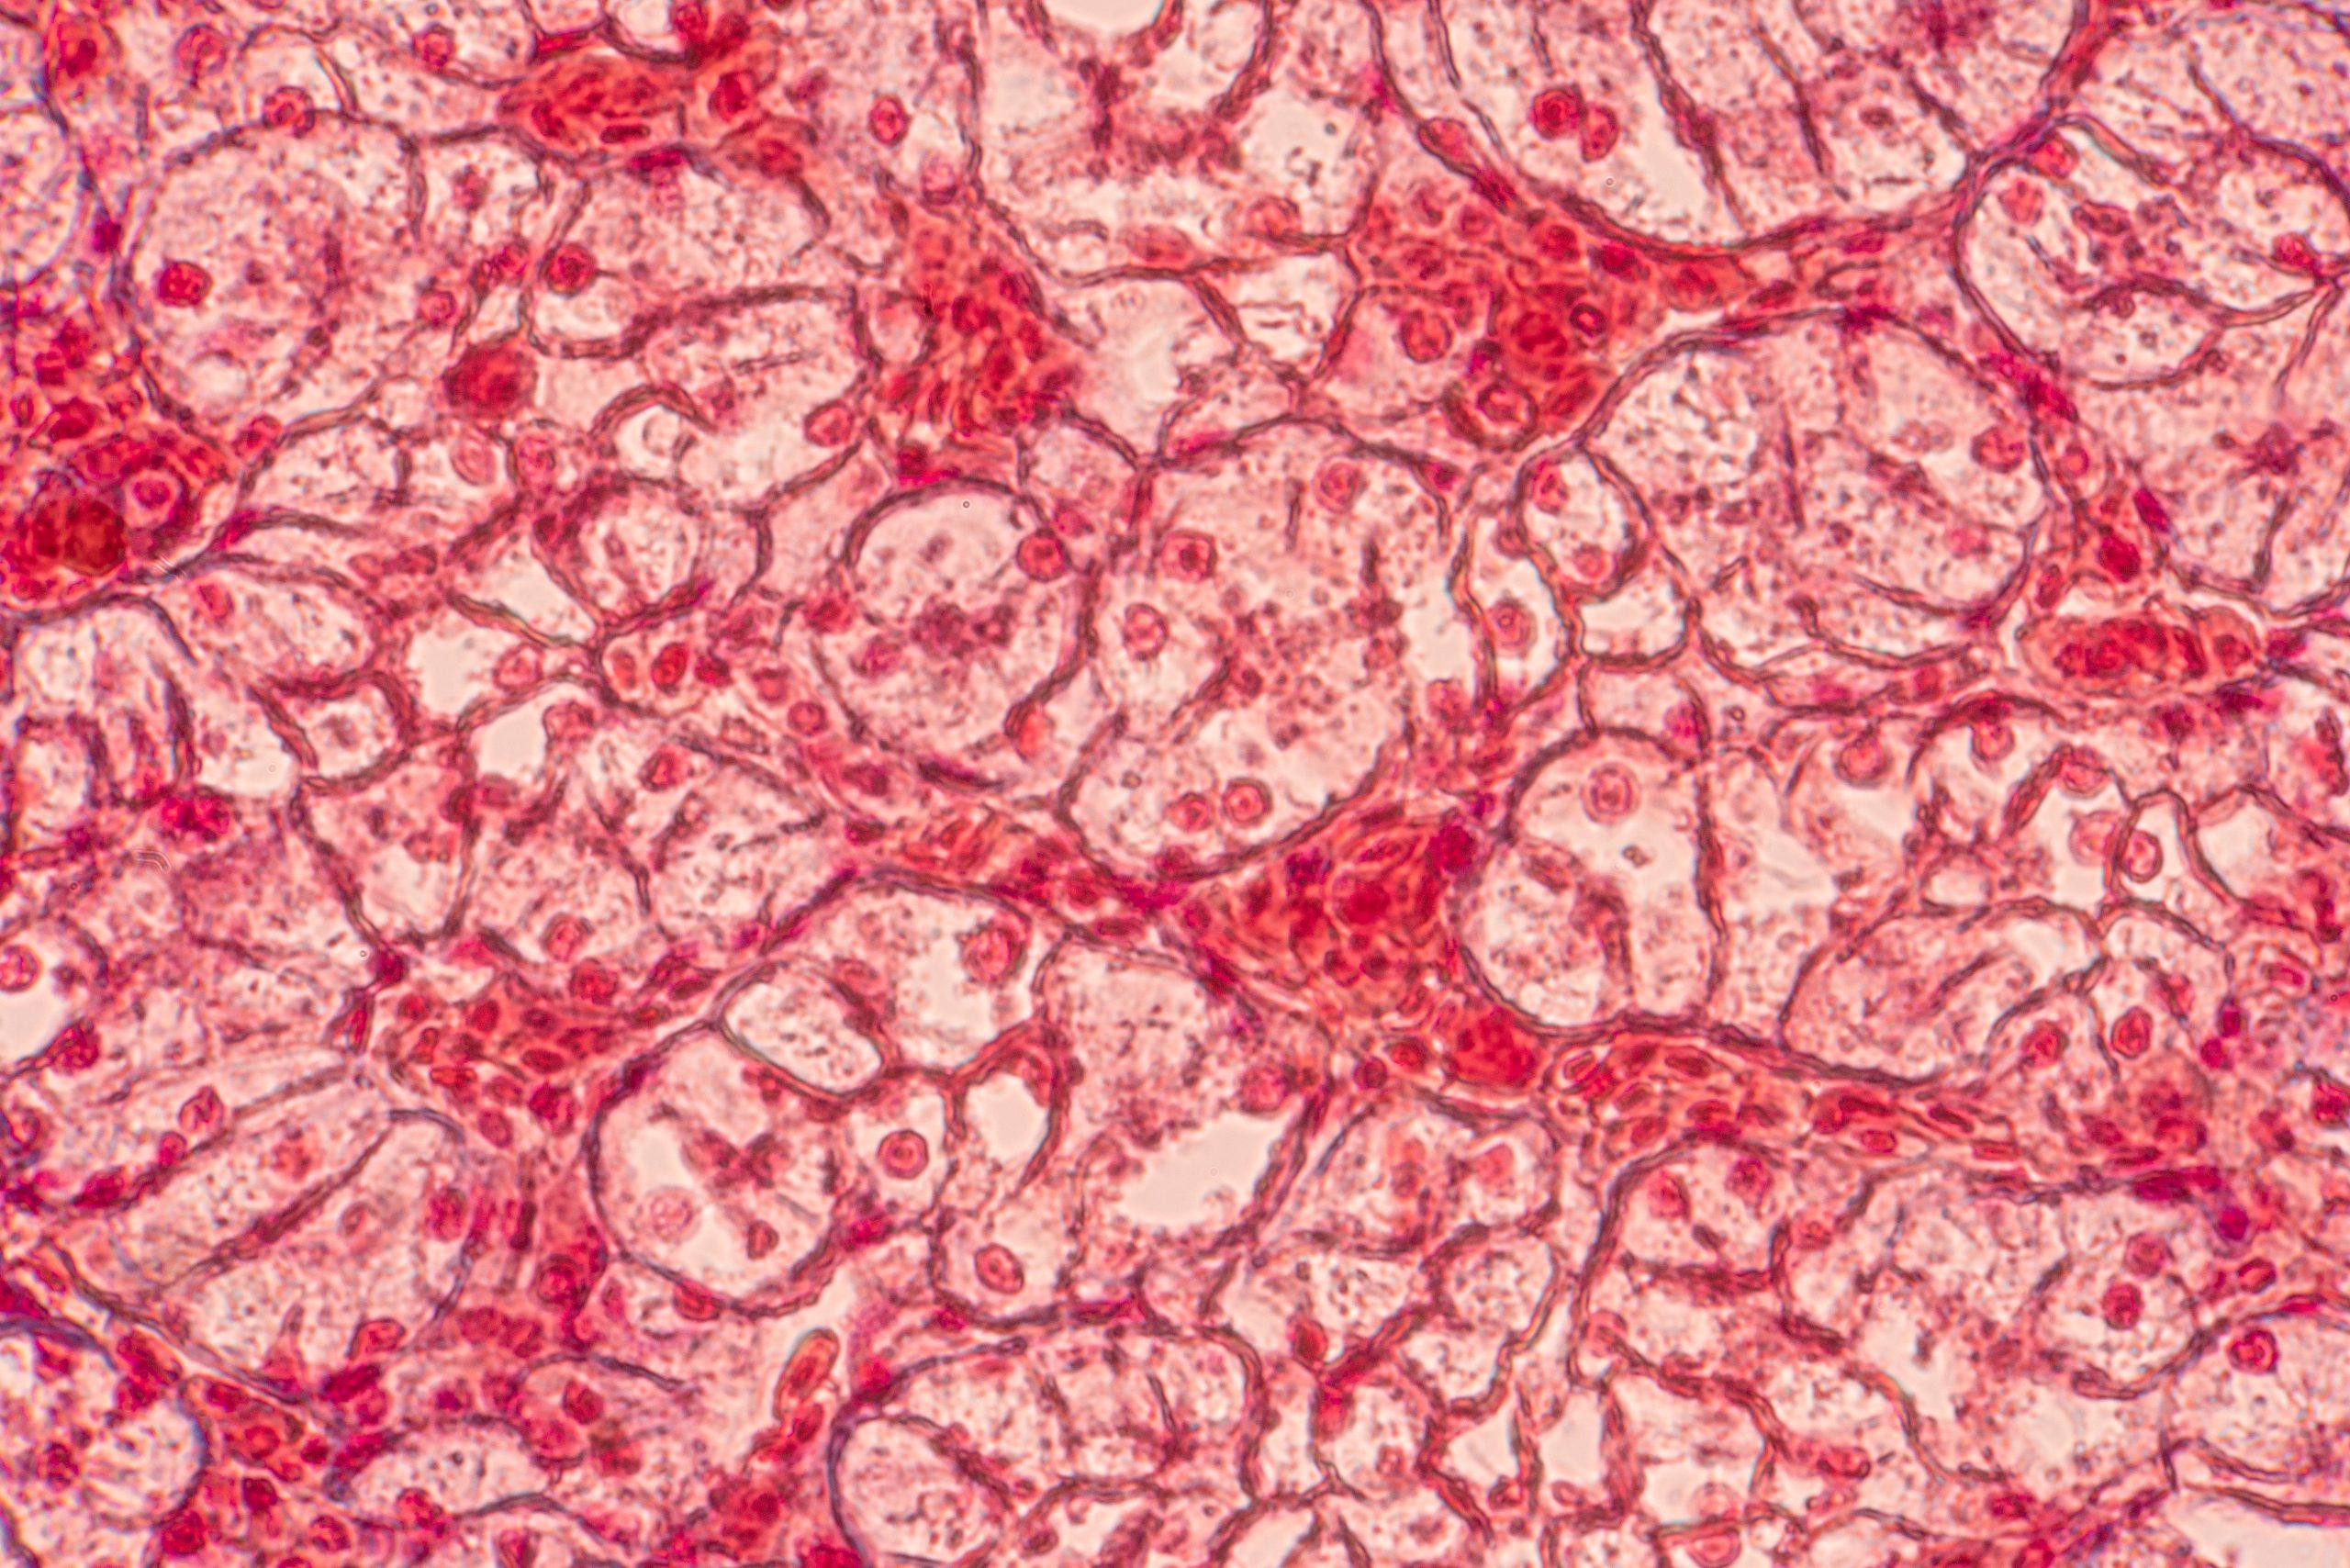

Centauri Therapeutics has published data showing that CTX-09’s ability effectively clears drug-resistant Gram-negative bacteria through a novel dual mechanism, marking a promising development for new infection therapies.